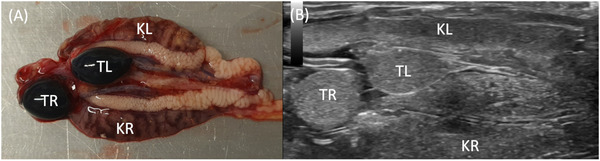

泌尿生殖道的评估在蜥蜴的疾病诊断中具有重要意义,超声检查是最适合的影像学检查方法。然而,对于大多数通常饲养的物种,没有可用的参考数据。这项前瞻性解剖分析研究的目的是超声检查四种最常见的蜥蜴物种的泌尿生殖道,并比较它们的肾脏、睾丸和卵巢。其中包括41种蜥蜴、14种胡须龙、15种豹壁虎、7种面纱变色龙和5种豹变色龙。使用了8-18 MHz曲棍球棒传感器和6-15 MHz线性传感器。记录各器官的矢状面和横切面图像。所有蜥蜴的肾脏、19只蜥蜴中的18只蜥蜴的睾丸和22只蜥蜴中的13只蜥蜴的卵巢都能被观察到。本研究结果可为今后对上述物种的研究提供参考价值。

The assessment of the urogenital tract is of great importance in the diagnosis of diseases in lizards, and sonographic examination is the most suitable imaging method for this purpose. However, reference data are not available for most of the commonly kept species. The objective of this prospective anatomical analytical study was to sonographically examine the urogenital tract of four of the most commonly kept lizard species and compare their kidneys, testes, and ovaries. A total of 41 lizards, 14 bearded dragons (Pogona vitticeps), 15 leopard geckos (Eublepharis macularius), seven veiled chameleons (Chamaeleo calyptratus), and five panther chameleons (Furcifer pardalis) were included. An 8-18 MHz field hockey stick transducer and a 6-15 MHz linear transducer were used. Sagittal and transverse images of the organs were recorded. The kidneys could be visualized and assessed in full length in all lizards, the testes in 18 of 19, and the ovaries in 13 of 22 lizards. The results of the current study could serve as reference values for future studies on the species mentioned.